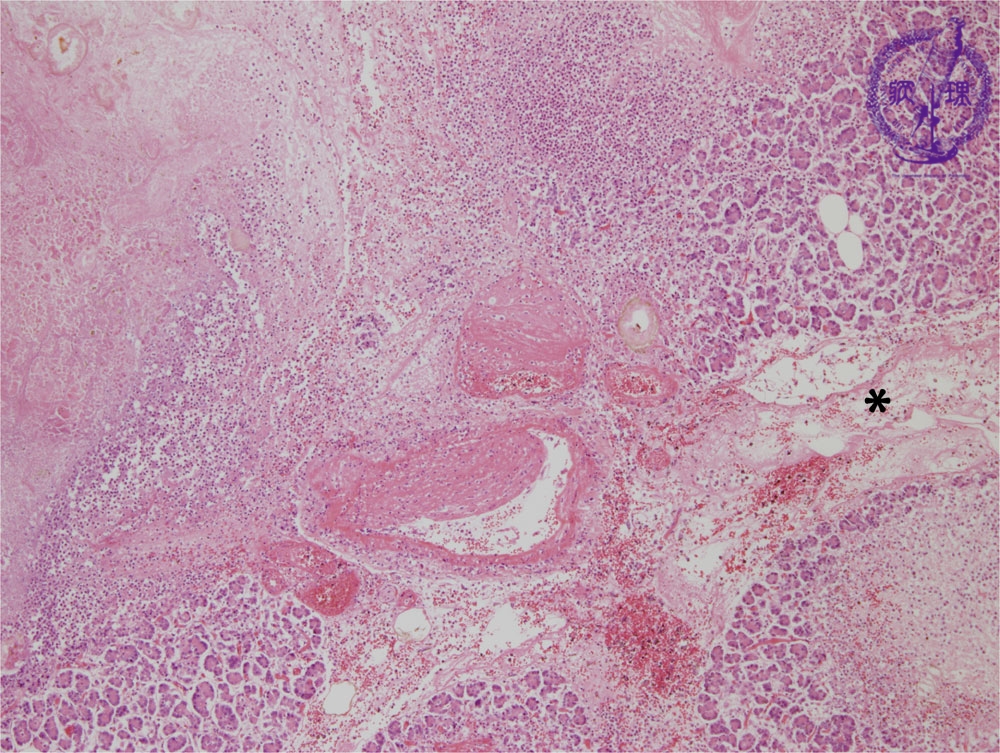

Microscopic image(HE stain, low power):There is destruction of interlobular blood vessels with pancreatic parenchymal necrosis. The majority of inflammation is seen within the pancreatic parenchyma.The interlobular space (*) shows edema and lymphectasia.